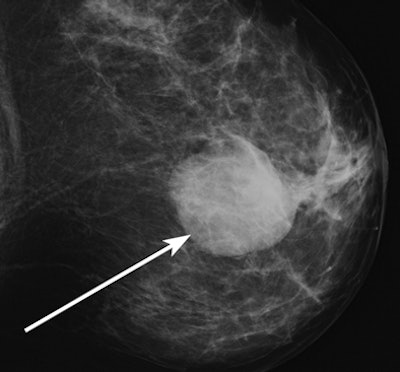

| Mammographic image of a high-density mass (arrow). |